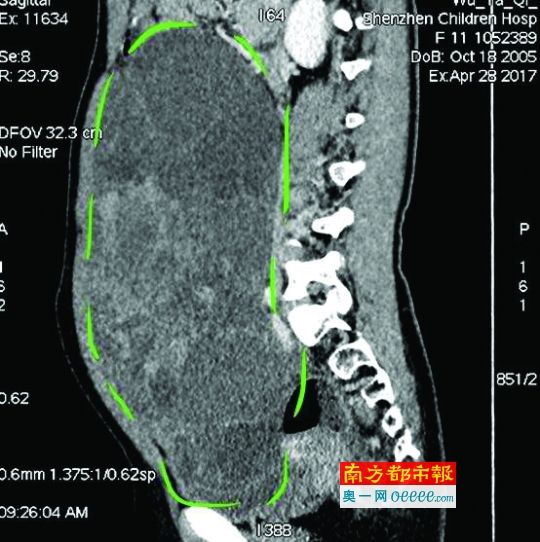

CT檢查圖像。

入院后,普外一科肖東主任向家長詢問了病史,仔細進行了體格檢查,并完善腹部CT。CT結果提示,孩子的大部分腹腔、盆腔被一個巨大的腫瘤占據,腸道、血管和腎盂都受到了不同程度的壓迫。從C T上看,腫瘤很可能起源于左側的卵巢。

手術中發現,小琪腹中的腫瘤體積巨大,大小約為25×20×15厘米,表面光滑,來源于左側卵巢。醫生們首先將其與周圍的組織小心剝離,然后將這個占據孩子腹腔、盆腔大部分的巨大包塊完整切除,切除腫瘤后還重建了左側卵巢。剖開瘤體,發現瘤體為囊性及實性混合組成,瘤體內部充盈著粘液狀的液體,重量達到了3000克。術后小琪病情穩定,測量腹圍從術前的72厘米減小到了62厘米。